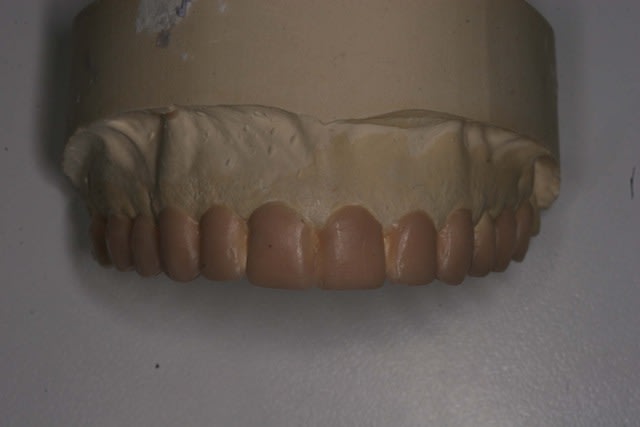

Voila la suite pour le maxillaire, le wax est fait sur arti en fonction de l'OIM obtenue après ortho. seule la 27 restera intacte.

Préparation des molaires pour permettre des RTE sous digue à travers les provisoires, retrait des anciennes couronnes et ancrages sur les 12, 15 et 25 endo satisfaisantes (couronnes ayant plus de 30 ans pour certaines!!!.

Tailles parallèles pour zircone 13 à 23 seront solidarisées pour éviter une migration post ortho.

Gingivectomie légère à la fraise à biseau pour harmoniser les collets, mais l'ortho a permis d'énormément faciliter ce travail.

Wax1 uh3wqn - Eugenol

Les dents du haut sont plus longues que les dents du bas, il semble.

Manque de longueur des incisivives du haut,

ratio largeur:longueur pas idéal

Pour tes centrales, elles sont un peu courtes.

Voir dessin fait rapido.

Les collet sont trop horizontaux.

Pour la centrale et la canine, ils devraintt être plus haut que la lattérale.

Une centrales doit faire entre 10 et 12 mm en hauteur, avec un rapport largeur sur longeur de 75-80 %

La 11 est aussi plus carrée que la 21